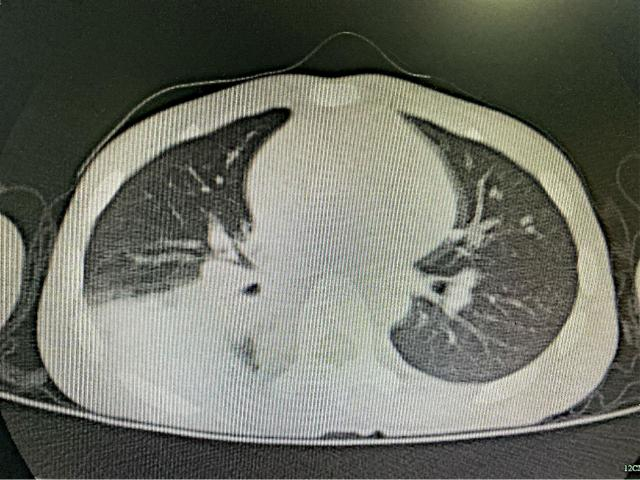

吴主任详细查看病历,孩子已经药物治疗3天,但病情依旧在加重,体温越来越高。肺部CT可见,病灶范围越来越大,并且伴有右肺的大片的不张和实变。

在气管镜下,可以看到孩子的右肺下叶支气管已完全被痰栓阻塞……经过灌洗治疗,医生成功地从右肺下叶灌洗出一根“千年老参”——支气管塑形。